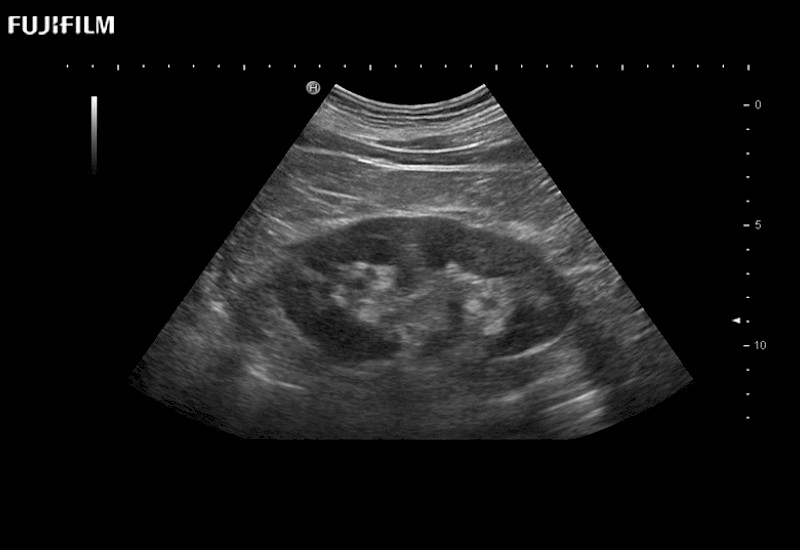

The ARIETTA 650 DI combines trusted Fujifilm Healthcare technologies and features tailored for surgical oncology.

Designed to meet the demands of surgeons, the ARIETTA 650 DI offers precise guidance. Its advanced capabilities and large, intuitive display offer accurate and efficient care in operating rooms and specialized surgical settings.